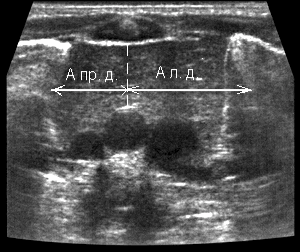

| Фото. На продольном срезе правой (А) и левой доли (В) измеряют длину и толщину (передне-задний размер), а на поперечном срезе (Б) — ширину долей. | ||